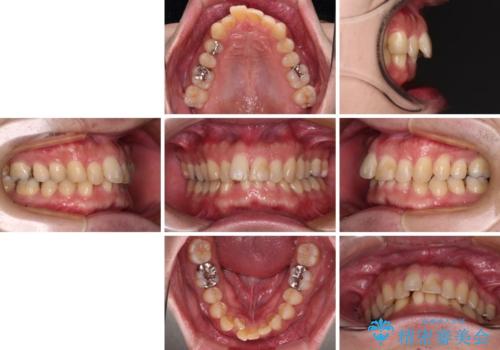

- 深い咬み合わせによる食いしばりで、顎関節や頭が痛むことがあるとのことで来院された患者様です。

歯ぎしりができないくらい強い食いしばりの咬合状態であったため、奥歯の歯軸を起き上がらせることで咬合を挙上させ、歯ぎしりができるようにしていくこととしました。

インビザラインでの矯正治療も可能でしたが、自己管理の煩わしさを嫌ってワイヤー装置による矯正治療を行うこととしました。

下顎が左側にずれているため、上下正中は最大限合わせられるところまで合わせるゴールとなりました。